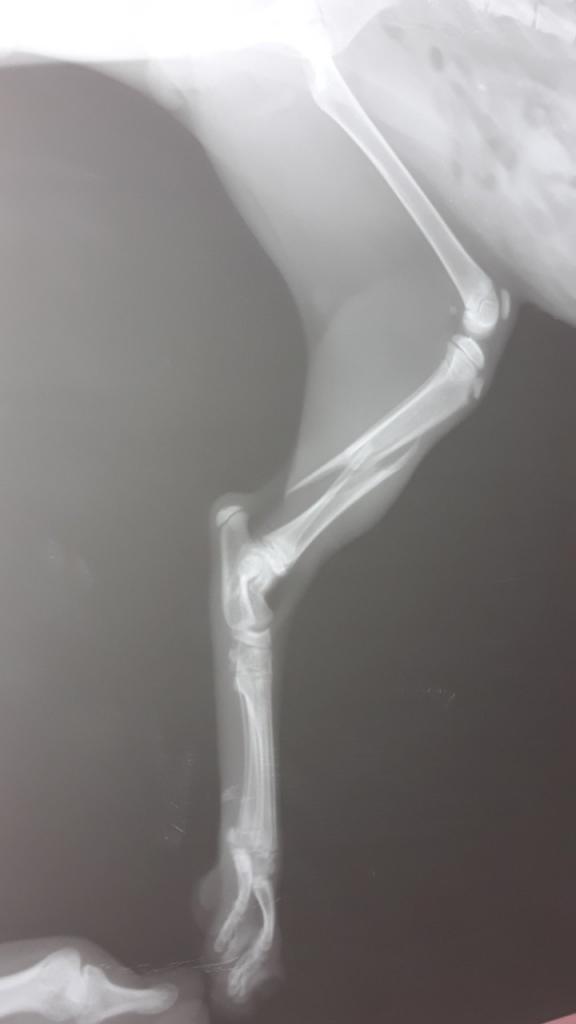

Помогите спасти котёнка ,его выбросили с 9-го этажа, у него перелом 3-х лапок,перелом таза и забита грудная клетка...!!!!((((

Он лежит на реабилитации в клинике на Сахарова 36...Не безразличные люди собрали уже 1000 гривен.Операция стоит около 3 тыс. гривен.